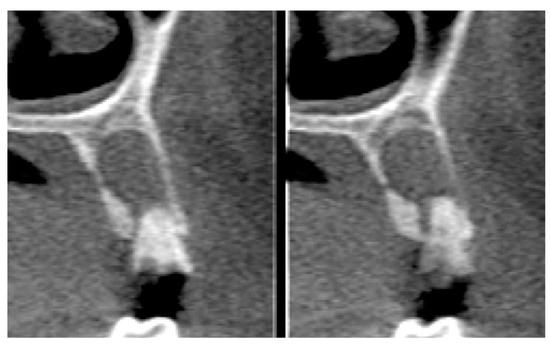

Socket Preservation Using a (Dense) PTFE Barrier with or without Xenograft Material: A Randomized Clinical Trial

2.6. Tomographic Analysis

| Parameter | Before | After | ||

|---|---|---|---|---|

| Mean | Standard Deviation | Mean | Standard Deviation | |

| Buccal plate | 5.55 | 1.73 | 6.01 | 2.33 |

| Socket height | 9.10 | 1.50 | 8.69 | 1.48 |

| Cervical third | 7.46 | 0.73 | 6.57 | 1.12 |

| Medium third | 7.80 | 1.00 | 7.15 | 1.10 |

| Apical third | 8.10 | 1.17 | 8.18 | 1.32 |